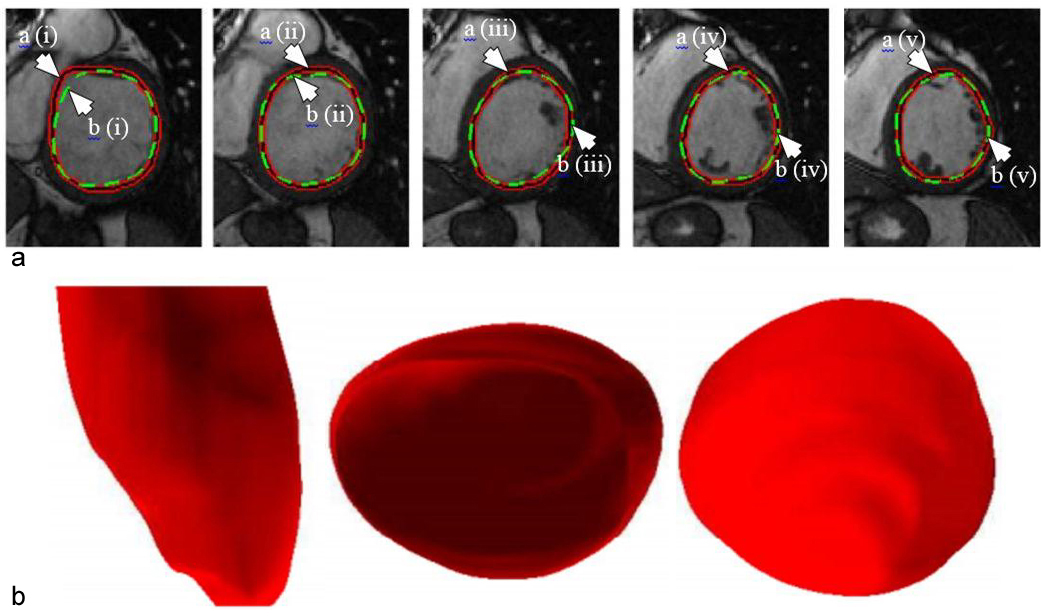

where denotes the step size, i represents successive iterations and represents change in with respect to time. The model with respect to the system is given in Figure 10. The 2D and 3D segmentation outputs are shown in Figure 11 (a) and Figure 11 (b). Dice metric (DM), average perpendicular distance (APD) and conformity metrics were computed from the output estimated and GT contours. The results have shown improvement over previous methodologies with DM at 0.94, APD at 1.81 mm and conformity at 0.86.

Figure 11(a). Example of outputs from the DL-based LV segmentation. The auto detected LV contour is shown in red-black as pointed by arrow (a) while GT contour is shown in green as pointed by arrow (b) (reproduced with permission from (42)). (b). Inferred 3D shape from the given model with side, top and bottom cut-sections (reproduced with permission from (42)).